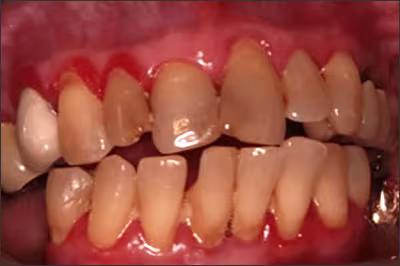

Figure 8.

Recognizable signs of established gingivitis include red, edematous, bleeding gums.